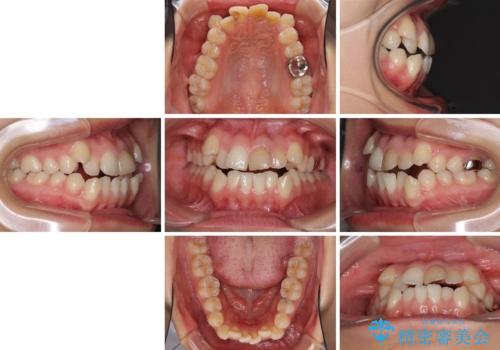

- 上の八重歯を気にして来院された患者様です。

受け口傾向にあるため、上顎前歯の叢生解消とともに下顎前歯を後方へ移動させることを目的とし、上下左右の第一小臼歯4歯を抜歯することとしました。

受け口傾向の方の下顎抜歯矯正では、下顎前歯の歯肉が退縮することがあります。前歯を移動させるときには、歯肉退縮が起こらないように工夫する必要があります。